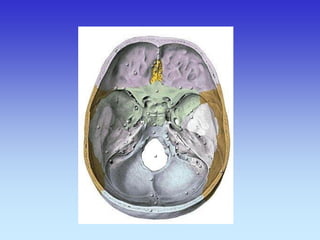

BAZA LUBANJE

BAZA LUBANJE - CT